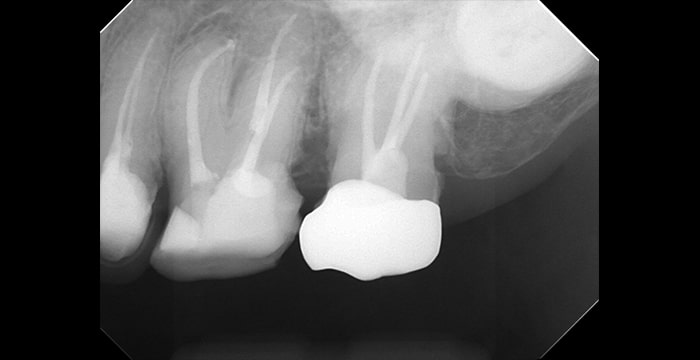

● Before

● After

精密根管治療の症例

-

根管治療後のレジンビルドアップ

根の治療を行った後の歯にレジンという歯科用プラスチックを盛って、従来の歯の形態を回復しました。

適応ケースに限りはありますがご希望の方はご相談ください。

治療費 130,000円(税別)+40,000〜80,000円(税別)